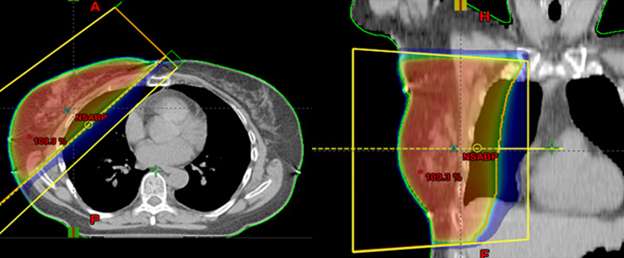

Below is an example of a case here at UCLA where we were able to spare the majority of the implant from receiving unnecessary radiation while achieving optimal coverage around the lumpectomy cavity.

Example of a partial breast case done at UCLA in a woman with breast augmentation who had a SAVI applicator placed. One can see that the distribution of the radiation dose as can be seen in the colored lines is focused around the lumpectomy cavity and that the majority of the implant (light grey) is spared from unnecessary radiation. A different view of the same patient with the SAVI applicator in the lumpectomy cavity just above the implant outlines in yellow.